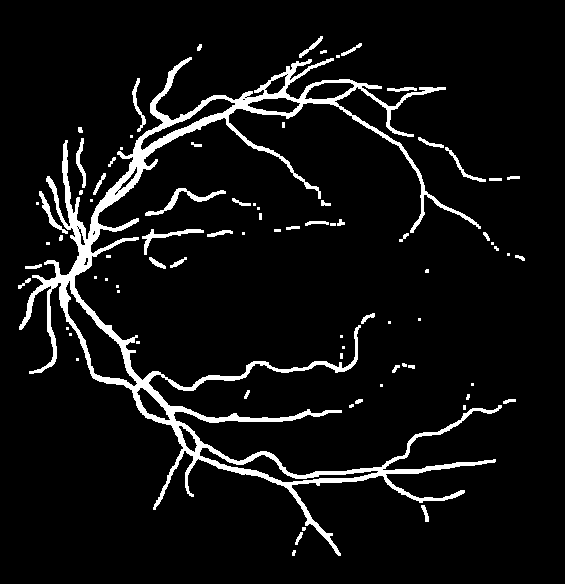

To justify the performance of our model, we compare the 4 metrics with 8 representative previous works from all 3 open-access datasets. The comparison results presented in Table 1 show that our MP-Net model outperforms the state-of-the-art methods regarding accuracy and in all three datasets, which meter the practical prediction quality and the overall prediction quality independent on thresholding specifications. The advancement is greater in the DRIVE dataset. It’s related to the fact that the DRIVE dataset contains more thin vessels, which is the main target of our model. Specificity is also the highest in DRIVE and CHASE_DB1 while sensitivity is highest in STARE. Particularly, our method outperforms ML-UNet [2] and JL-UNet [4] which adopt a different multi-class approach to also especially tackle the thin-vessels challenge. Figure 2 shows an example of our segmentation maps on DRIVE. As can be seen, most thin vessels and boundary areas have been meticulously picked up.